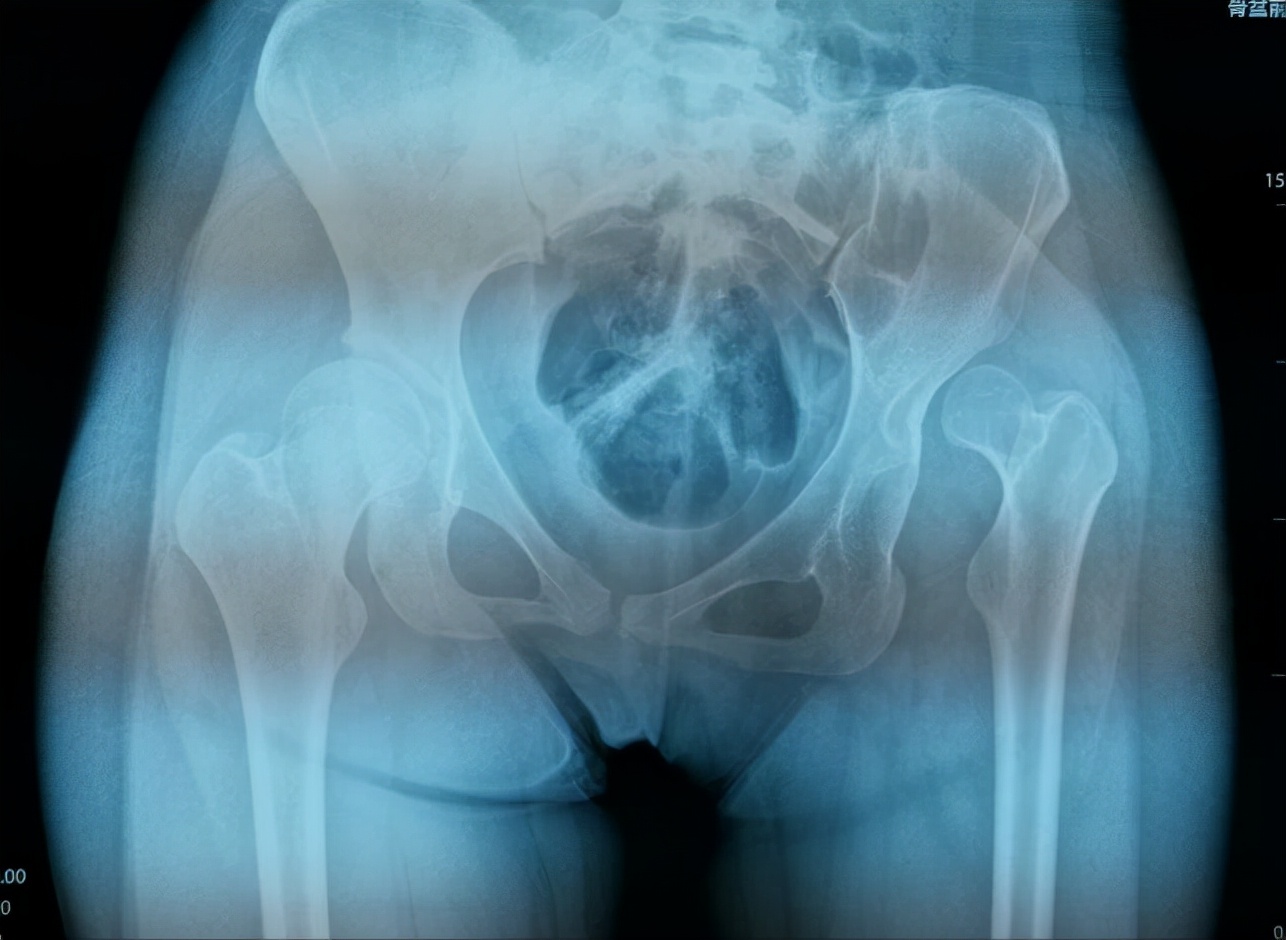

通过小张的的骨盆X线可以看到,她的左侧髋臼是一个发育不良的状态,髋臼较小较浅,外展角较大,而股骨头已经完全脱位,根据脱位高度分型为DDH(developmental dysplasia hip,发育性髋关节发育不良)IV型,已经属于最严重的程度了。

双下肢不等长

(骨盆正位片)